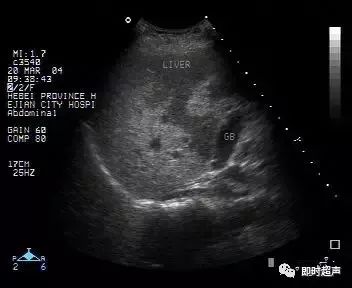

超声表现:

1、肝实质回声细密增强,呈云雾状,后方回声衰减。

2、肝内管道结构显示欠清。

3、肝肾对比阳性,正常情况下肝脏回声略高于肾实质回声,脂肪肝时肝脏回声明显增强。

4、肝脏增大,形态饱满,边缘变钝。

轻度:肝回声增强,后方回声衰减不明显,肝内管道结构显示正常。

中度:肝回声明显增强,后方回声衰减,肝内管道结构显示欠清晰。

重度:后方回声衰减明显,后方肝组织显示不清,膈肌显示不清。